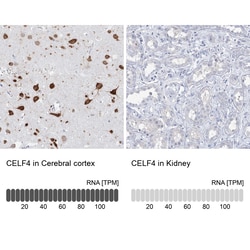

Immunogen sequence: MYIKMATLAN GQADNASLST NGLGSSPGSA GHMNGLSHSP GNPSTIPMKD H Highest antigen sequence identity to the following orthologs: Mouse - 100%, Rat - 100%.

Members of the CELF/BRUNOL protein family contain two N-terminal RNA recognition motif (RRM) domains, one C-terminal RRM domain, and a divergent segment of 160-230 aa between the second and third RRM domains. Members of this protein family regulate pre-mRNA alternative splicing and may also be involved in mRNA editing, and translation. Multiple transcript variants encoding different isoforms have been found for this gene.

| Gene | CELF4 |